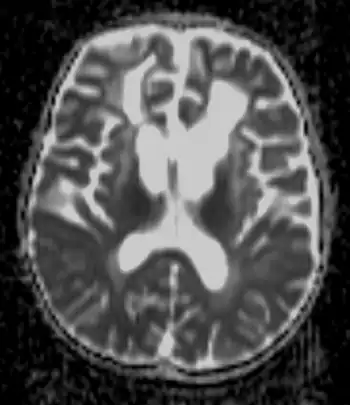

| Brain of a 4-year-old boy with Alexander disease showing macroencephaly and periventricular leukomalacia (note brownish discoloration around the cerebral ventricles) | |